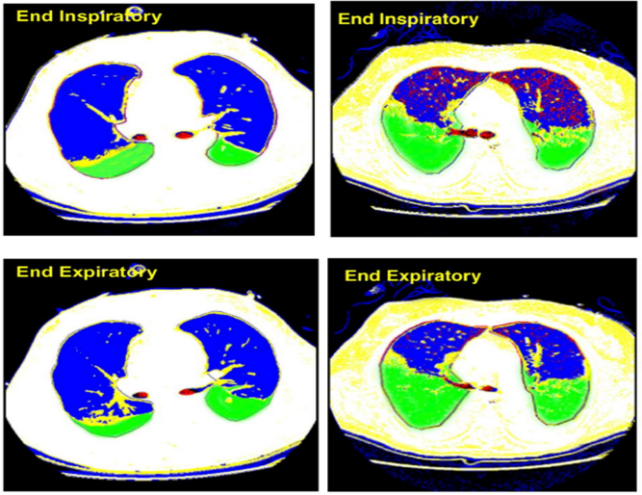

ARDS是非心源性肺水肿,机制为肺毛细血管渗漏,其特点是病变呈非均一性,在呼吸机支持时会出现呼吸机相关性肺损伤(VILI)。众所周知,VILI与容量相关,较大潮气量会引起严重的容量伤;同样,压力(包括平台压和驱动压)增高也会造成VILI。当驱动压>14 cmH2O,患者的生存明显下降。为了维持肺泡的开放,机械通气需要适当的PEEP,如果PPEE过高,也会造成VILI,并与患者的生存密切相关,高PEEP患者死亡率增加。此外,在机械损伤的同时也增加了生物伤,在VILI严重区域,炎症因子明显增高(下图右上红色区域[1]

图片

图源:Am J Respir Crit Care Med, 2007, 175:160-166.